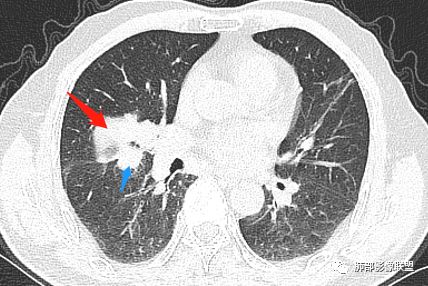

主病灶在中叶,但是左肺舌段叶有条索影,陈旧病变。蓝色箭头支气管受压,是淋巴结肿大

主病灶在中叶,但是还有结节状病变在下叶

叶间裂推移方向

虽然是一个大的病灶,但是周围是比较散

边缘还有多发小灶

病灶明显平直,中央是粘液栓,低密度,分界清楚

吴婧老师和南边老师都对该病例进行了深入分析。从支气管管壁的增厚,支气管狭窄后扩张,支气管粘液栓,病灶形态,到病灶不均匀强化及坏死彻底,到周边病灶及肺组织空气的潴留,加之纵隔内淋巴结肿大伴钙化等等,都支持慢性炎性病灶,尤其是结核。

墨西哥仙人掌征---结核        影像上结核灶,粗大的均匀枝干,推测是支气管囊状扩张引起的,在非支气管区,形成圆形坏死囊群;如果这些坏死比较稀薄,又遇到扩张支气管,就会形成粗大的“墨西哥仙人掌”。结核引起的支气管近端炎症纤维化,可以造成支气管阻塞,从而将干酪样坏死物封堵在管腔内。仙人掌主干内部应该是干酪为主,稀薄的,具有流动性,时间久了会出现钙化。

结核坏死与鳞癌鉴别有一点是结核坏死没有方向性,鳞癌有。鳞癌靠近支气管近端部分,血供容易维持,不易坏死,所以坏死靠外侧。而结核干酪样坏死,把一定体积的流动性坏死物,包裹起来,什么形状最省料?坏死物包裹,表面积最省的自然是圆球形,而遇到支气管,坏死物一多,就把支气管撑大了。包裹物是就地取材,扩张的支气管就成了包裹结构。